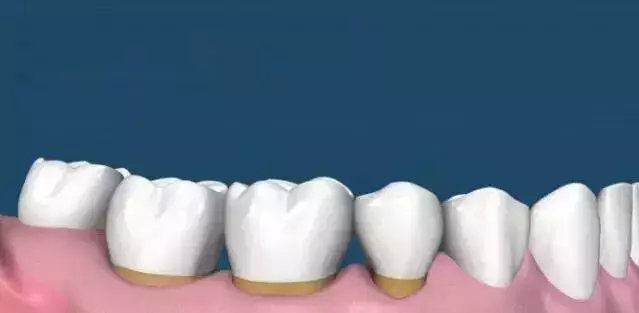

广大口腔专家说——其实刷牙只能清除牙齿表面和舌苔上的食物残渣,而牙线也只是清除牙间隙内的脏东西,但牙齿背面却一直是个死角位置,牙垢一旦钙化,牙齿背面将会成为牙周病的“第一案发现场”。那我们该怎么办呢?答案只有一个:洗牙!